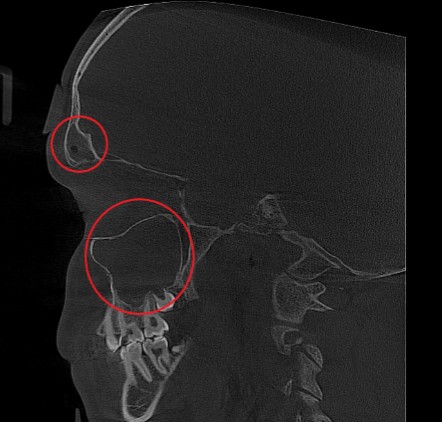

Проведена компьютерная томография околоносовых пазух, которая подтвердила наличие правостороннего гемисинусита (воспаление нескольких пазух с одной стороны), как следствие периодонтита зуба 1.6.

Представлено КЛКТ околоносовых пазух до начала лечения. Выделена зона воспаления пазух.